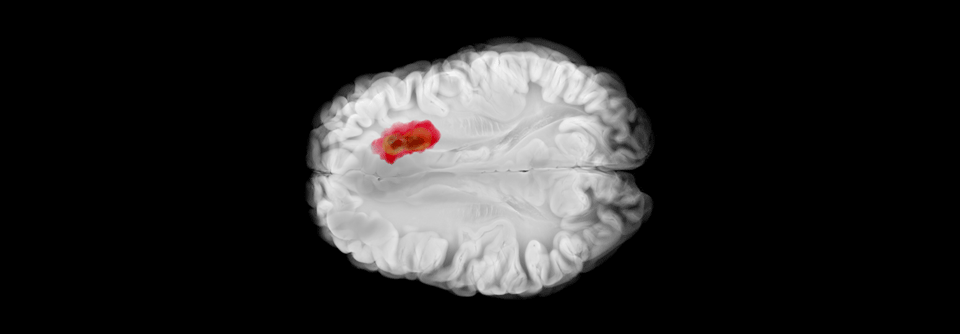

Outcome nach Schlaganfall

Wie sich der Erfolg einer Thrombektomie unterstützen lässt

Die Thrombektomie brachte 2015 in Sachen Outcome nach Schlaganfall einen großen Durchbruch. Dennoch bleibt weiterhin ein großer Teil der Betroffenen…